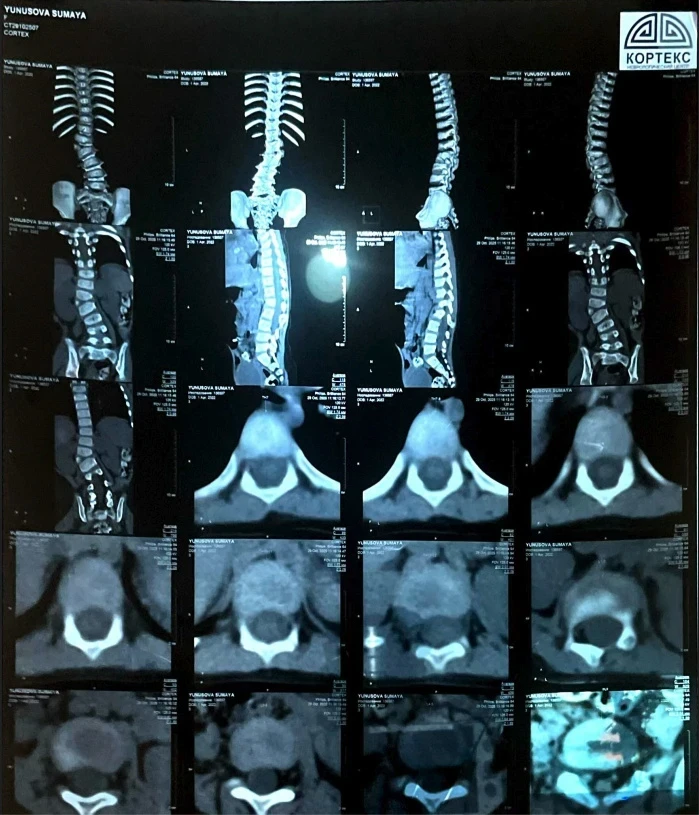

"Трудно ходить и бегать". Сумае нужна операция для исправления сколиоза

У девочки выявили сколиоз сложной формы, что вызывает у неё затруднения при ходьбе и беге, и она вынуждена проводить большую часть дня в сидячем или лежачем положении.

«Узнав, что ничего не помогает, мы обратились за консультацией к турецким профессорам. Они заявили, что единственный выход — операция, и чем быстрее она будет проведена, тем лучше для роста и развития Сумаи. Кроме того, мы узнали, что у неё есть лишняя кость на позвонке, что также является последствием сколиоза», - сообщает мама.

Сколиоз уже вызвал асимметрию тела, у Сумаи одно плечо ниже другого, а одна нога короче.

«Мы не знали, что сколиоз может привести к таким серьёзным последствиям, пока не столкнулись с этим сами. Мы проходили обследования, стараясь, чтобы дочь росла и развивалась нормально. Но о том, что искривление позвоночника может сдавливать внутренние органы и вызывать сильные боли, мы даже не подозревали. Поэтому нам нужно спешить с операцией», - добавляет Мадина.